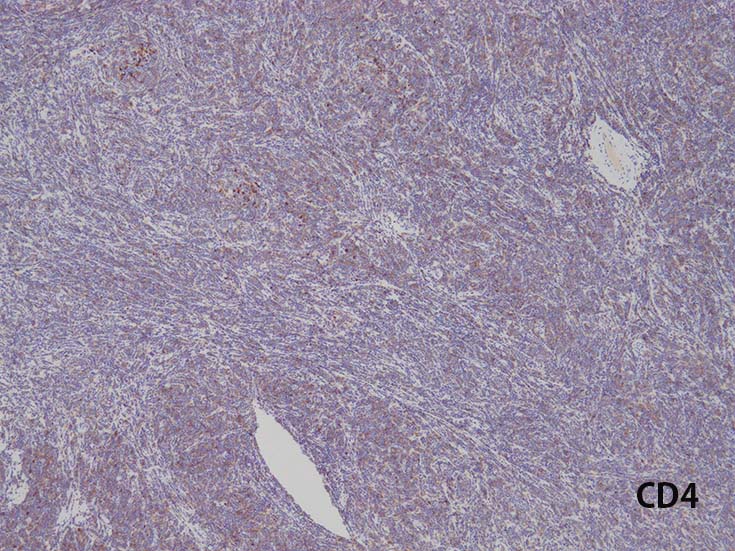

Immunophenotype of T-ALL/ LBL

- TdT, CD34に加えて, CD99と CD1a陽性はT-lymphoblastsの前駆細胞の性質を確認するのに役立つ.

- CD1a, CD2, surface CD3 (dim), CD4, CD5, CD8は種々の程度に発現する.

- T-ALL はしばしば, CD4とCD8の double positive となる. またCD10が陽性になる

- CD4,CD8 double positiveはT-prolymphocytic leukaemiaでも認められる. CD10もPTCL(第一にはAITL)に陽性となることに注意.